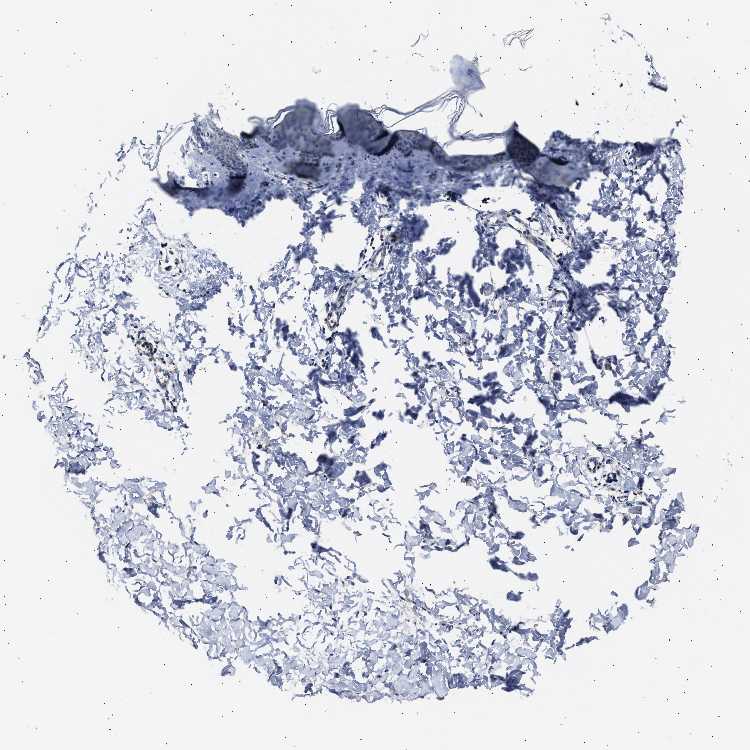

SKIN 1 - Antibody stainingi

Antibody staining in the annotated cell types in the current human tissue is reported as not detected, low, medium, or high, based on conventional immunohistochemistry profiling in selected tissues. This score is based on the combination of the staining intensity and fraction of stained cells.

Each image is clickable and will lead to virtual microscopy that enables deeper exploration of all samples and also displays staining intensity scores, fraction scores and subcellular localization as well as patient and tissue information for each sample.

Antibody HPA019087Antibody HPA020051

Langerhans -Not detected

Cells in basal layer Not detected-

Cells in corneal layer Not detected-

Cells in granular layer Not detected-

Cells in spinous layer Not detected-

Endothelial cells Not detected-

Extracellular matrix Not detected-

Fibroblasts -Not detected

Fibrohistiocytic cells Not detected-

Keratinocytes -Not detected

Langerhans cells Not detected-

Lymphocytes Low-

Melanocytes Not detectedNot detected

Vascular mural cells Not detected-